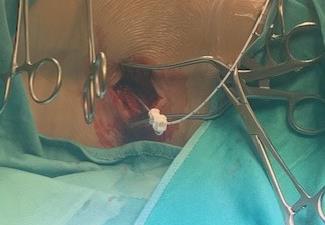

Adductor Longus L2, L3

Vastus Lateralis L3,L4

Tibialis Anterior L4, L5

Peroneus longus L5, S1

Gastrocnemius S1, S2

Abductor hallucis S1, S2

Sphincter S2